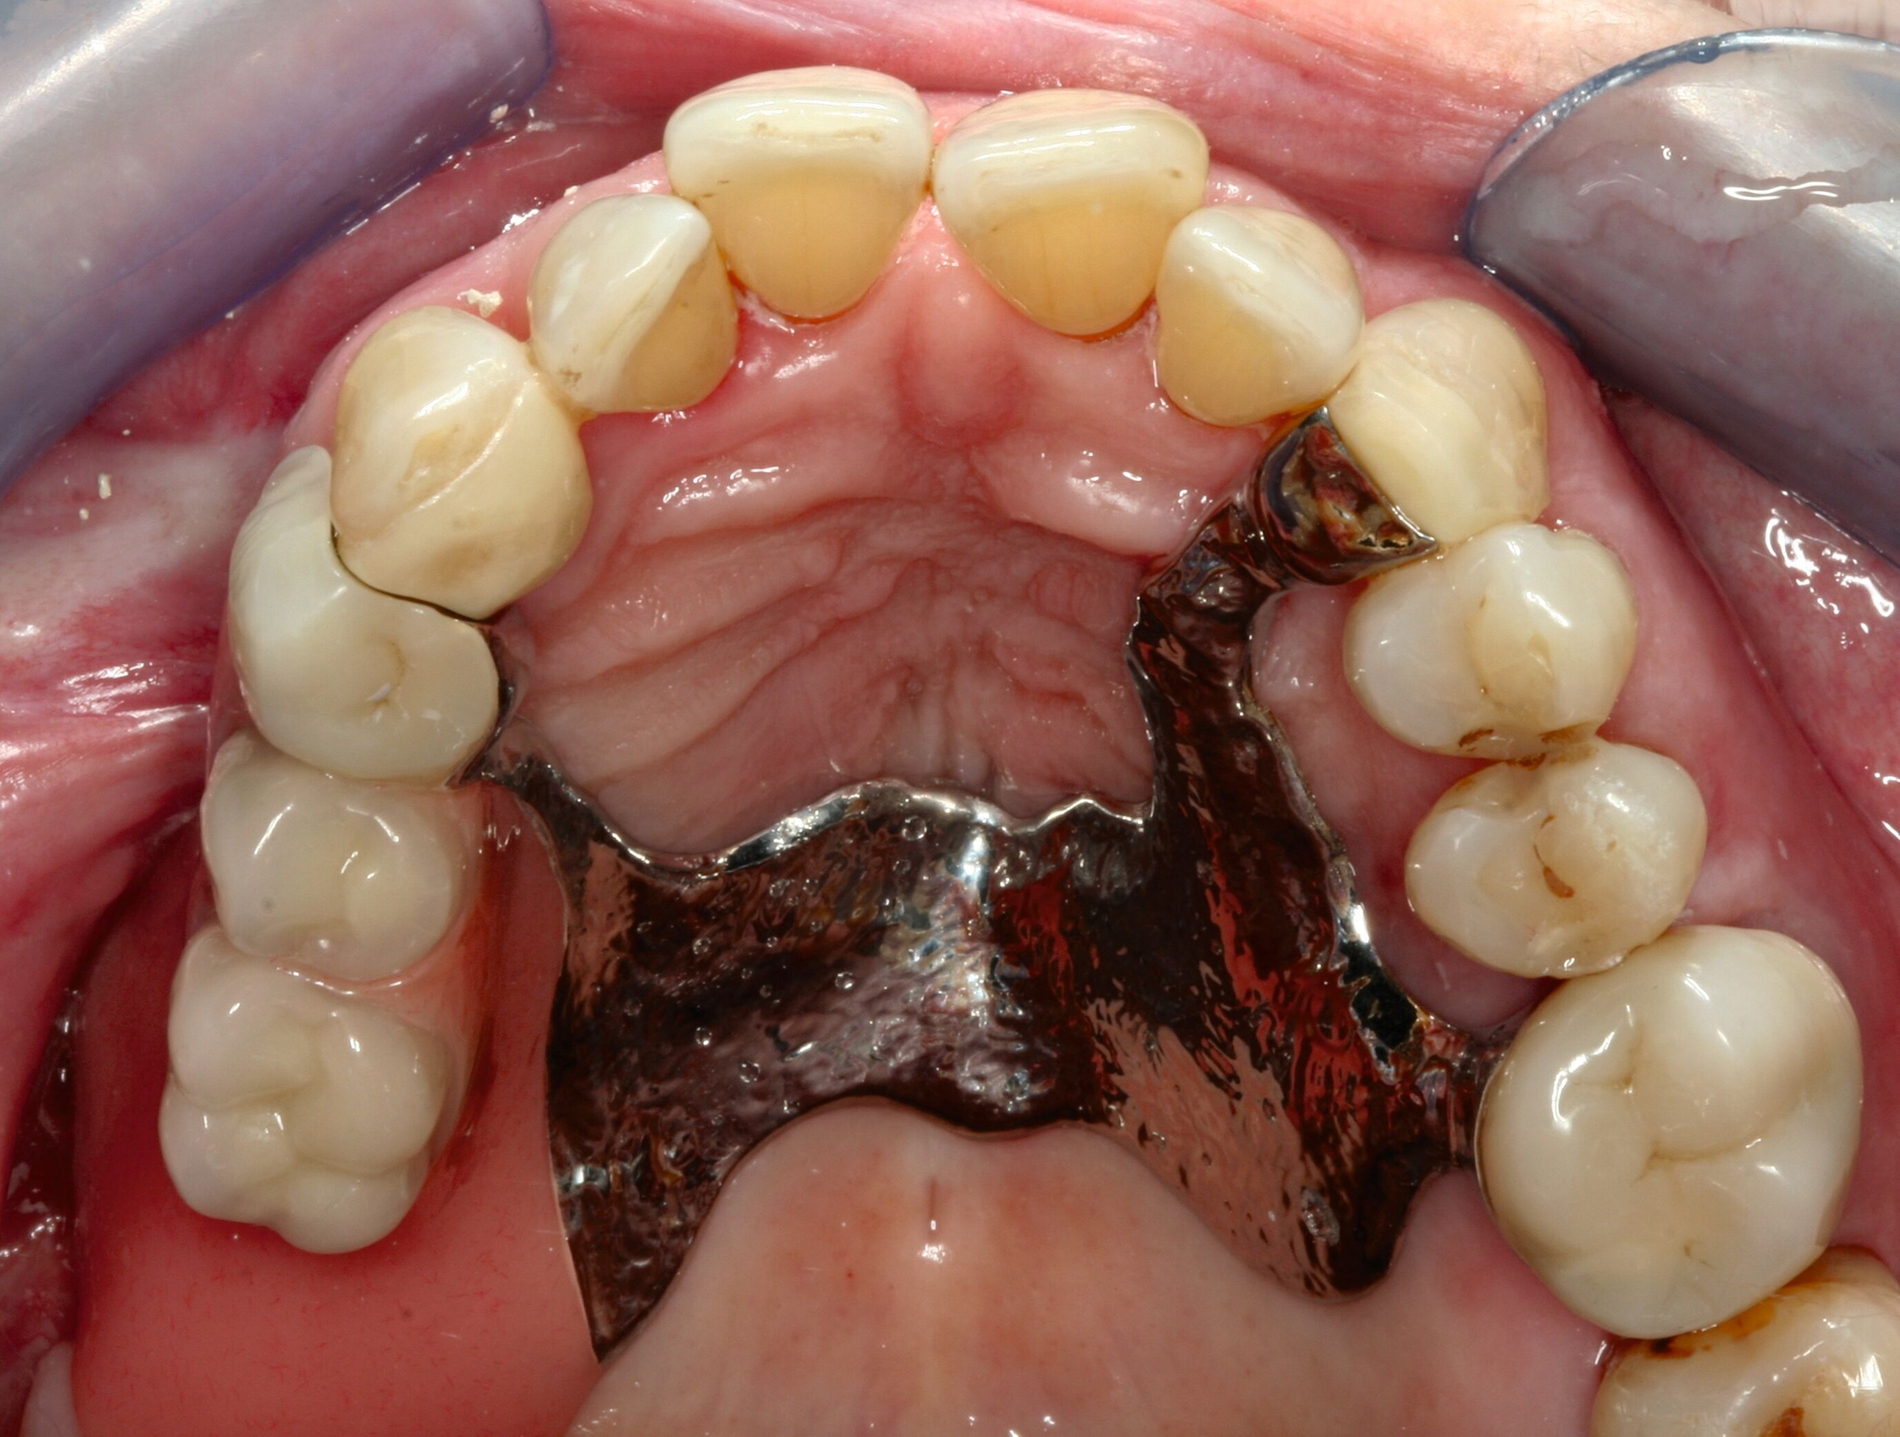

Eine 74-jährige Patientin erhielt eine Modellgussprothese im Oberkiefer zur Abdeckung einer Mund-Antrum-Verbindung infolge der Resektion eines malignen Befunds im Bereich des Alveolarfortsatzes rechtsseitig (Abbildung 1). Trotz mehrfacher Umarbeitungen gelang eine Adaption an den Zahnersatz nicht. Die Patientin empfand die Klammern als zu scharf und spitz. Zudem störte sie sich an der Ästhetik. Die Mundhygiene war gut, nur wenige Zähne besaßen eine Füllung. Es bestand eine hohe Erwartungshaltung an den Zahnersatz.

Bezogen auf die Belastbarkeit lagen zum damaligen Zeitpunkt trotz der Malignomtherapie keine Einschränkungen vor (BS 1). Dem Wunsch der Patientin nach einem Klammer-freien Zahnersatz konnte mit regulärem Therapieaufwand entsprochen werden (Abbildung 2). Nach dessen Eingliederung gelang eine rasche Gewöhnung. Die Patientin erschien viele Jahre regelmäßig zur professionellen Zahnreinigung und zur Kontrolle. Zahnmedizinische Interventionen waren nicht erforderlich.

Nach siebenjähriger Tragezeit reduzierte sich der Allgemeinzustand der Patienten bedingt durch einen zweifachen Apoplex erheblich. Die Angehörigen bemühten sich bei nun fehlender Eigenverantwortlichkeit der Patientin um eine dauerhafte Aufnahme in eine Pflegeeinrichtung. Eine Vorstellung zur zahnärztlichen Kontrolle erfolgte nicht und die Patientin konnte unter ihrer ursprünglichen Adresse nicht mehr erreicht werden. Nach eineinhalbjähriger Abwesenheit wurde die Patientin mit Unterstützung ihrer Angehörigen wegen reduzierter Nahrungsaufnahme aufgrund von Schmerzen zur zahnärztlichen Behandlung vorstellig (Abbildung 3). Bei stark reduzierter Therapie- und Mundhygienefähigkeit wurde zusammen mit den Angehörigen entschieden, mehrere stark kariös und parodontal geschädigte Zähne zu entfernen und den vorhandenen Zahnersatz umzuarbeiten. Es lag nun eine BS 3 bis 4 vor.